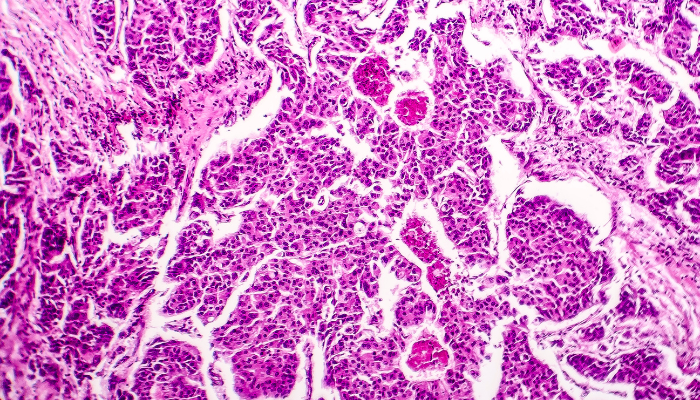

Un estudio de la Escuela Politécnica Federal (ETH) de Zúrich (Suiza) muestra que las metástasis del cáncer de mama se desarrollan de forma más acelerada durante la fase del sueño de las mujeres.

Pero el estudio de la ETH, publicado en la revista Nature y recogido por El Mundo, arroja que “las células cancerosas circulantes que posteriormente forman metástasis surgen principalmente durante la fase de sueño de los individuos afectados”. «Cuando la persona afectada está dormida, el tumor se despierta», afirma Nicola Aceto, líder del estudio y profesor de Oncología Molecular de la ETH.

En el análisis participaron 30 pacientes de cáncer y modelos de ratón. Allí, notaron que el tumor generaba más células circulantes cuando el individuo estaba dormido. También observaron que las células que abandonan el tumor por la noche se dividen más rápido; por lo tanto, presentan un mayor potencial para formar metástasis en comparación con las células circulantes que abandonan el tumor durante el día.

«Nuestra investigación demuestra que la huida de las células cancerosas circulantes del tumor original está controlada por hormonas como la melatonina, que determinan nuestros ritmos diurnos y nocturnos», agrega Zoi Diamantopoulou, investigadora de la ETH.